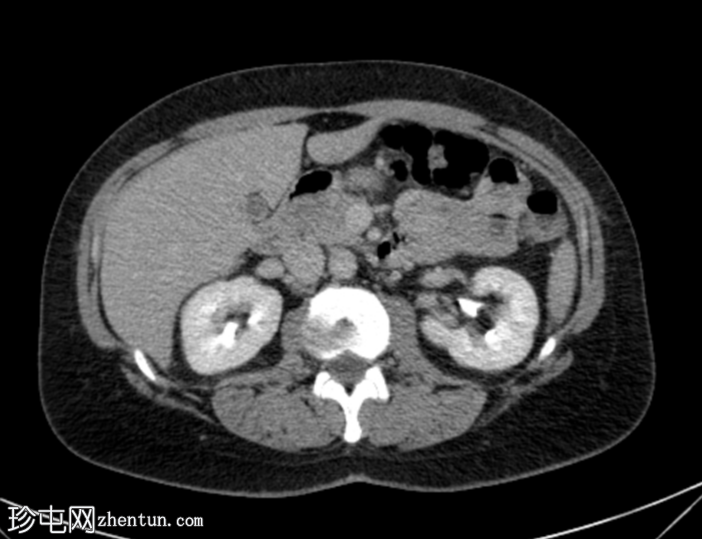

轴位增强扫描(门静脉期)

右肾轴位和冠状位图像均显示肾实质下部低强化区域,伴肾周脂肪间隙模糊,符合急性肾盂肾炎的

影像

学表现。

膀胱壁轻度环周增厚及强化,可能为轻度膀胱炎。